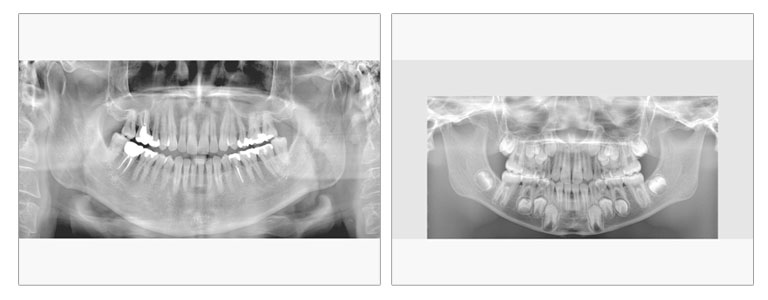

パノラマ

必要に応じて標準・幼児用・顎骨・直交のパノラマ撮影を切り替えられます。小児用パノラマ撮影では、お子様や顎の小さい患者さんに使用し、撮影範囲を小さくすることで、照射線量を低減することができます。